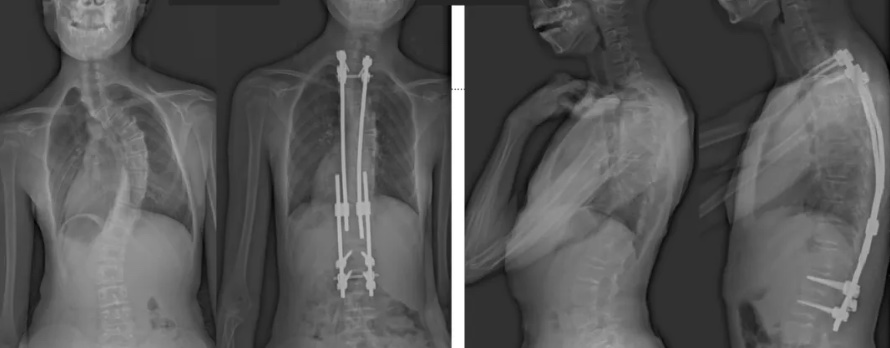

白瑪?shù)恼恍g(shù)前、術(shù)后對(duì)比圖(左側(cè));側(cè)位術(shù)前、術(shù)后對(duì)比圖(右側(cè))

術(shù)后第二天,白瑪就下地活動(dòng)了。媽媽驚喜地發(fā)現(xiàn),白瑪一下子“長(zhǎng)高”了近十厘米,重新抬起了頭,挺直了脊梁,肩膀也不歪了,可謂“脫胎換骨”。媽媽激動(dòng)地錄制了一段白瑪走路的身影,把喜悅分享給全家。白瑪?shù)男g(shù)后檢查也提示,手術(shù)成功,恢復(fù)良好。